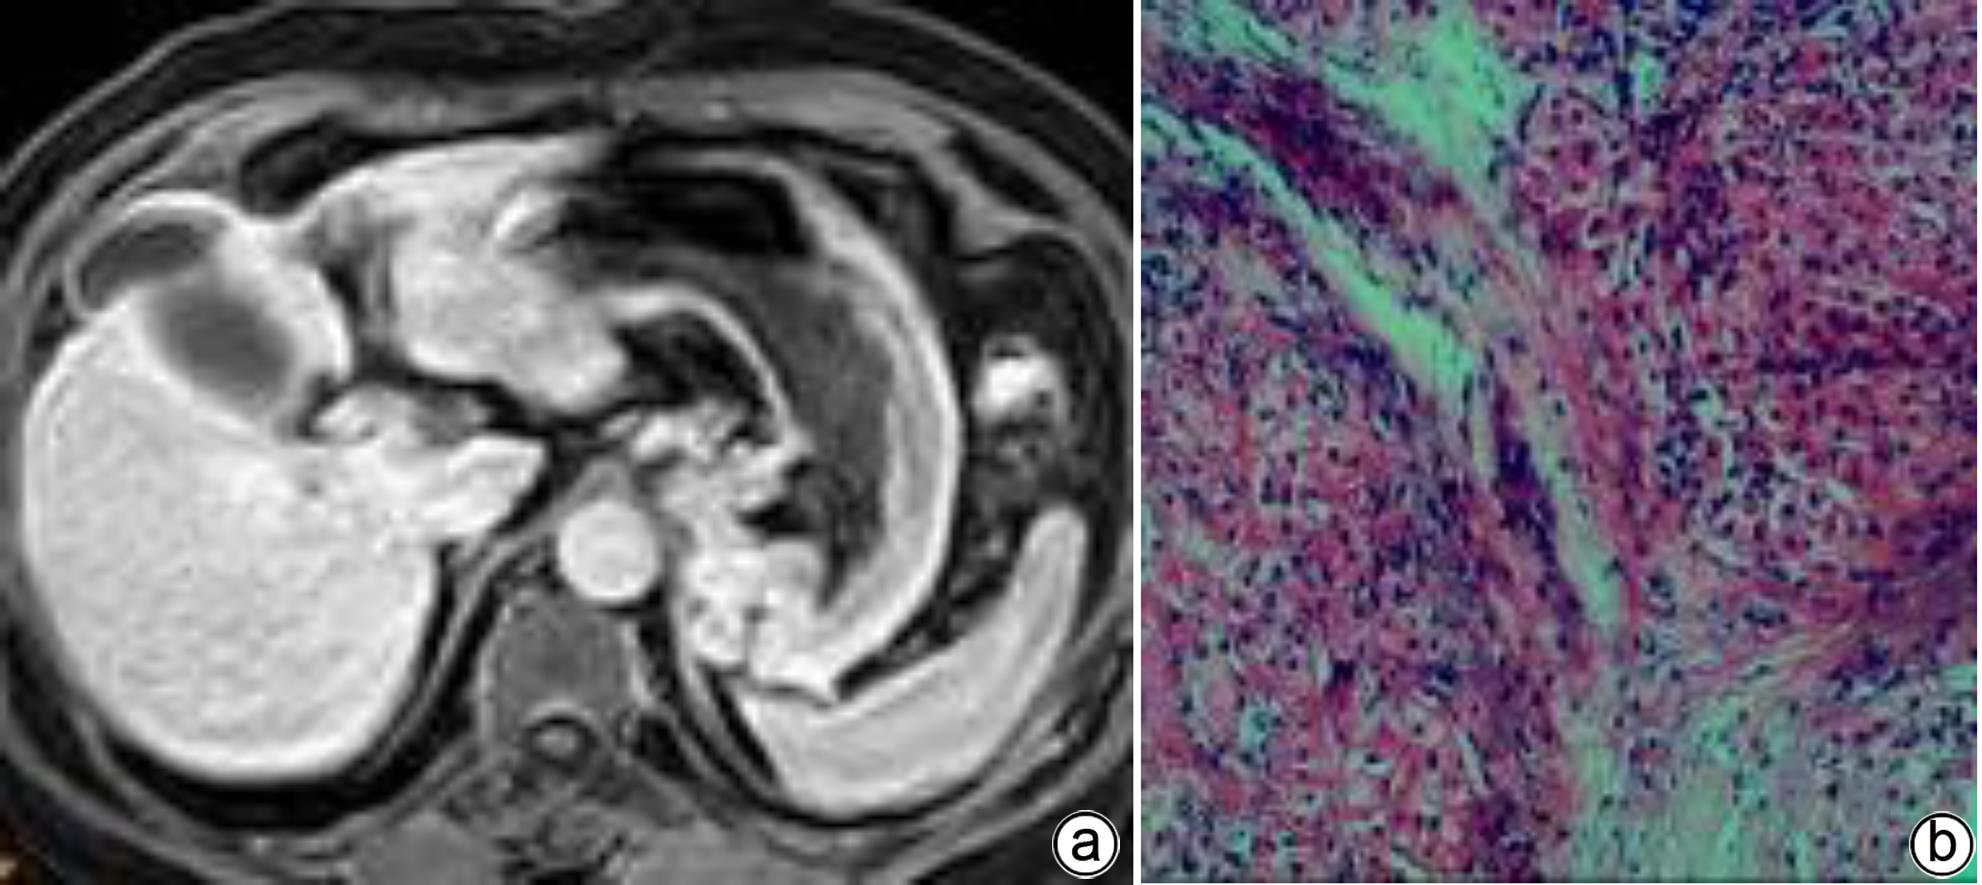

注: a,男,68岁,胆汁排泄期示,胆道各区均未见显影,胆道评分1分;b,肝穿活检病理(HE染色,×200),镜下见类圆形肝细胞团内的肝细胞排列稍紊乱,可见较多肝细胞水肿,部分细胞气球样变,小范围的点状坏死,汇管区扩大,淋巴细胞浸润,纤维组织增生并分割包绕肝细胞团。免疫组化:Hepar-1(+),HBsAg(+),CK7(+),符合慢性乙型肝炎改变(G2S4)。

图 1 肝纤维化S4期MRI增强扫描及肝活检病理结果

Figure 1. MRI enhanced scan image of the bile excretion phase of the S4 stage of liver fibrosis + Pathological image of liver biopsy